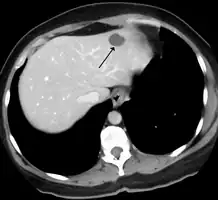

A liver hemangioma as seen on CT

Treatment